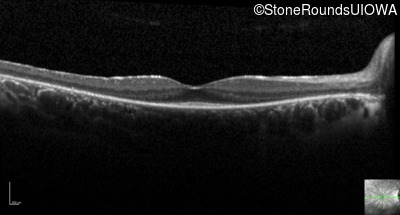

Optical Coherence Tomography - Right - 20/25 +2

Exemplar / OCT Stack

OCT Stack